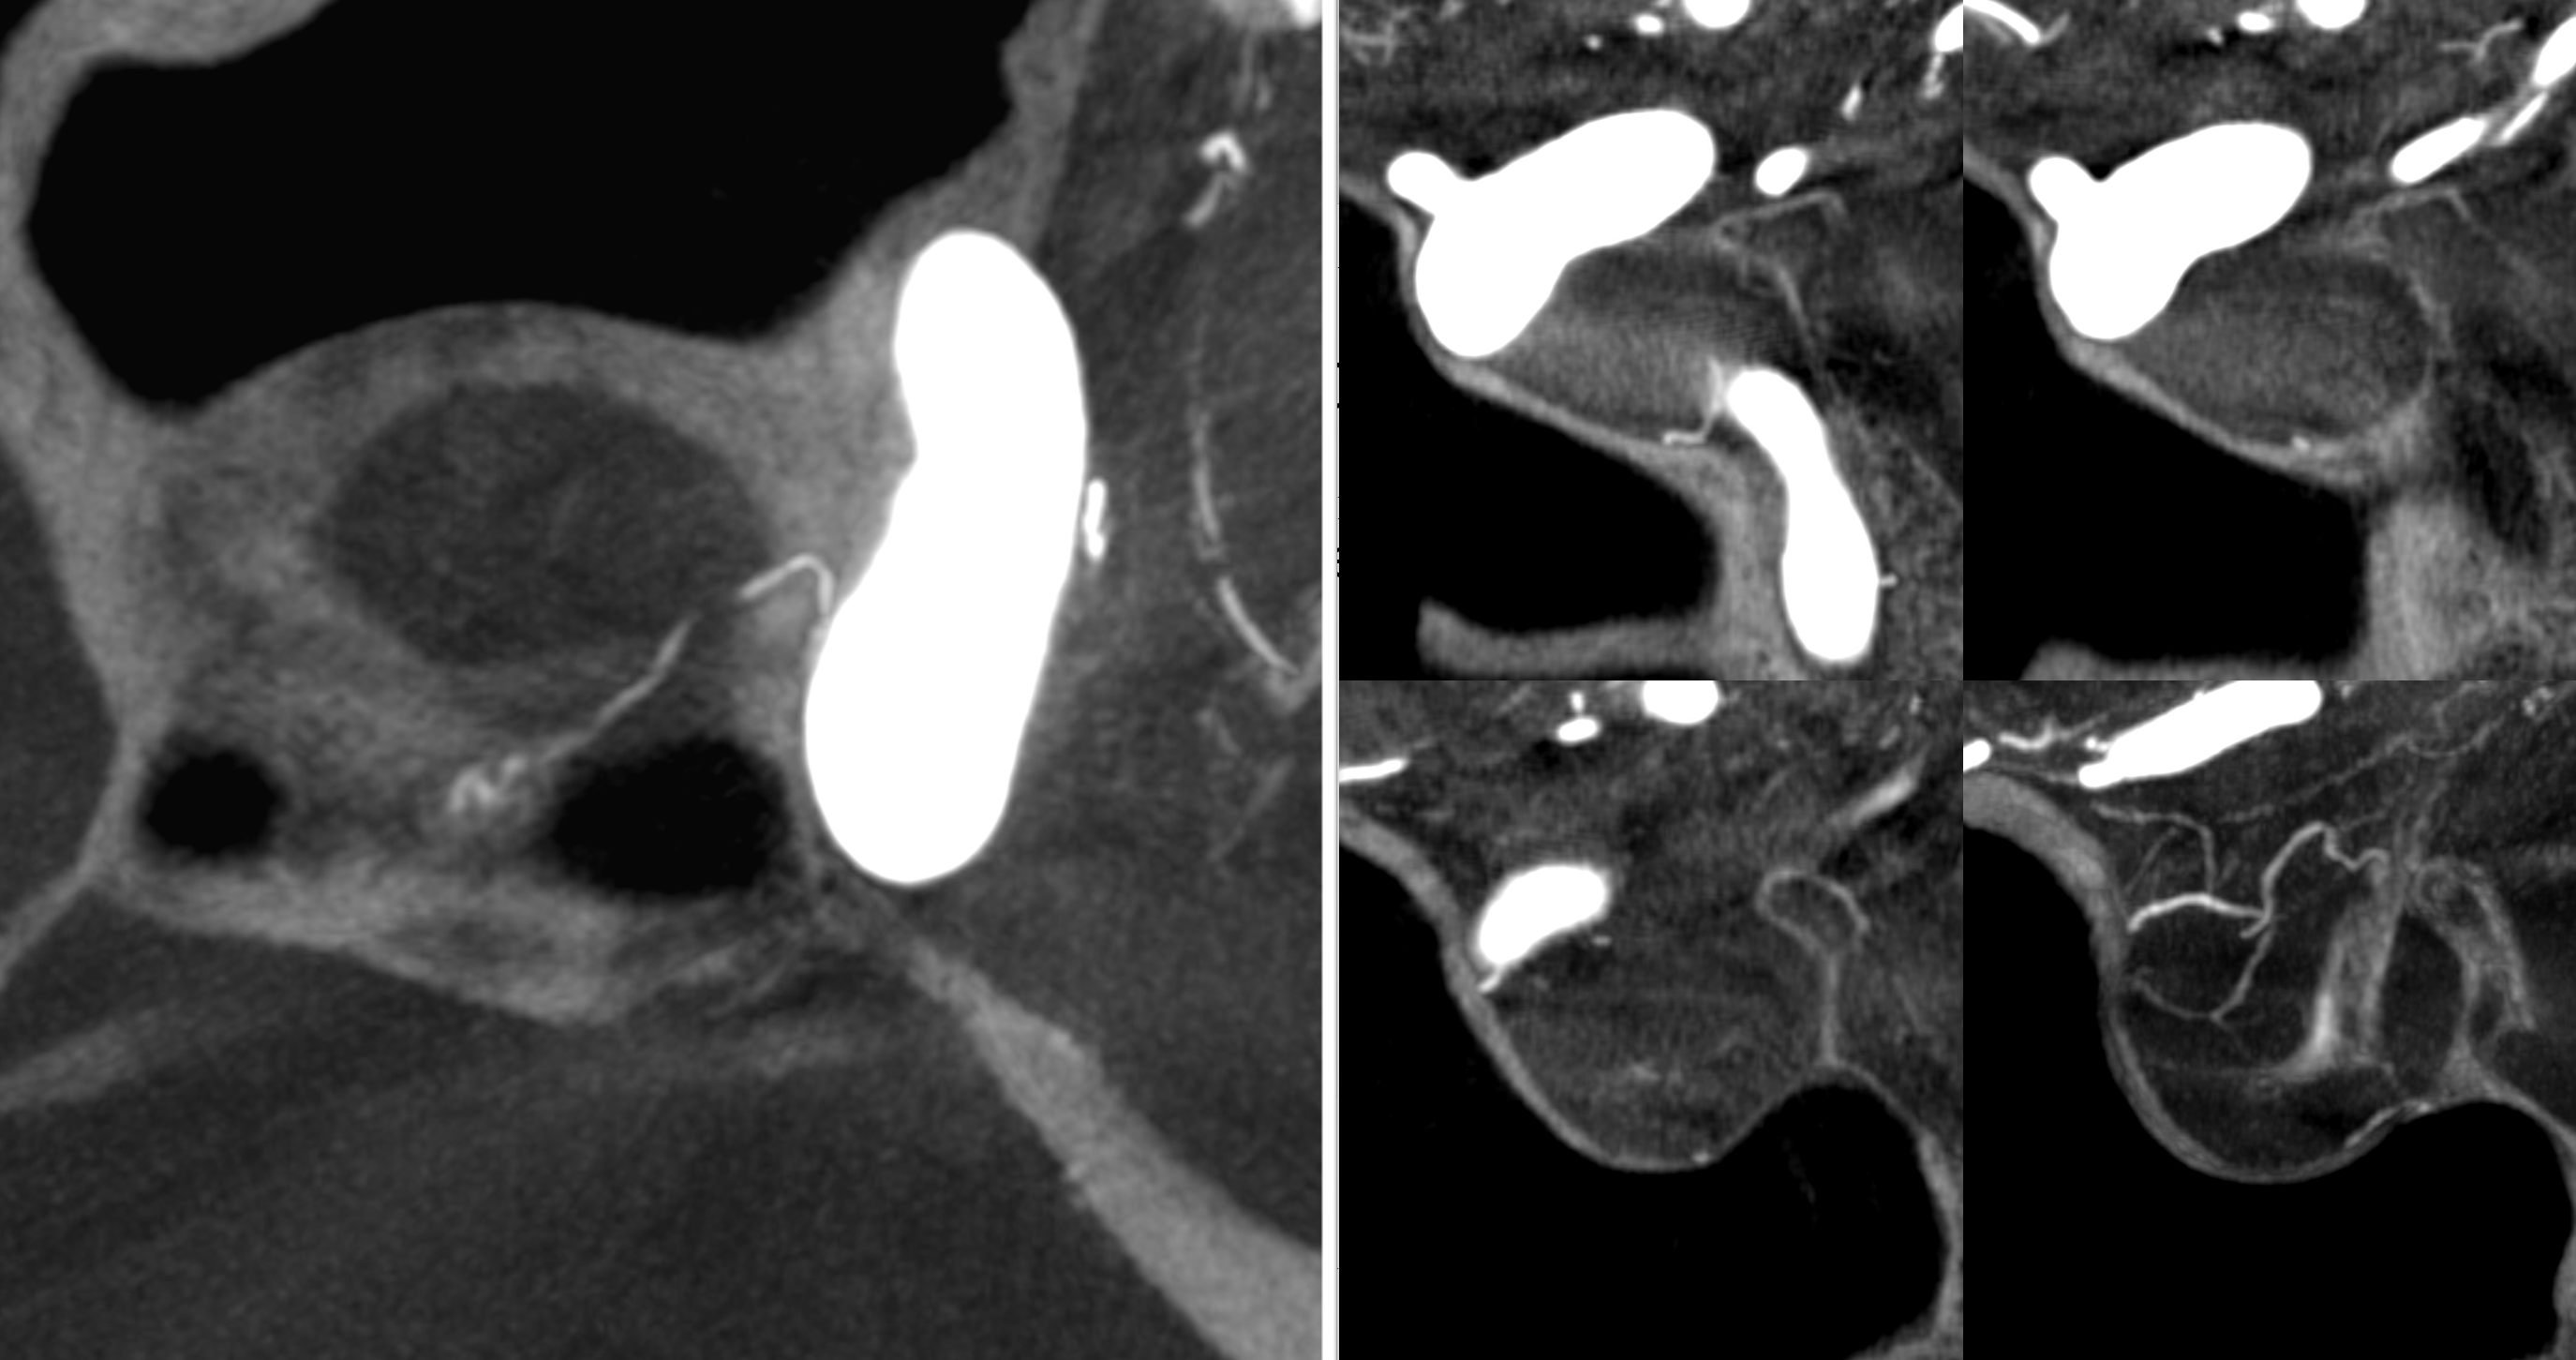

Power of Cone Beam CT imaging

Even the smallest superior hypophyseal arteries can be seen with advanced cone beam CT. Top left is an already high resolution cone beam CT volume rendered image with no apparent Superior Hypophyseal. Windowing to increase sensitivity allows for visualization of a tiny superior hypophyseal (arrow) — top right image. Bottom row are axial (left) and coronal (right) MIP images, showing the same artery, as well as beautifully seen pituitary stalk (dashed arrow)